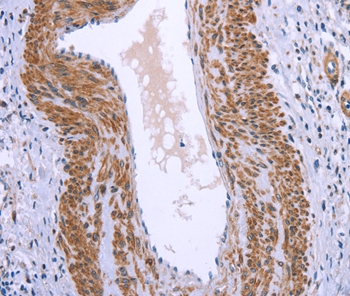

Immunohistochemical analysis of paraffin-embedded Human thyroid cancer tissue using #37601 at dilution 1/40.

Immunohistochemical analysis of paraffin-embedded Human cervical cancer tissue using #37601 at dilution 1/40.